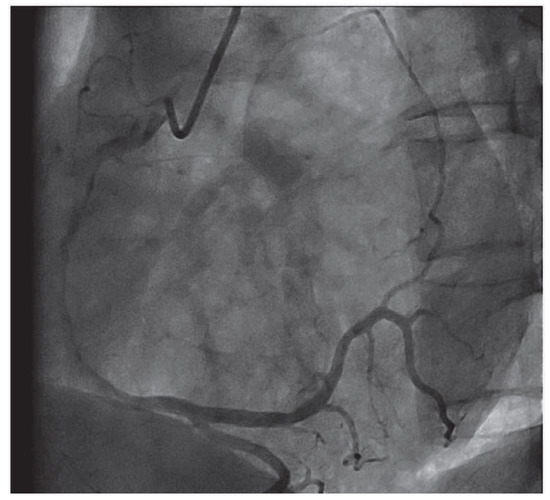

Valentine in the Heart

Case Report